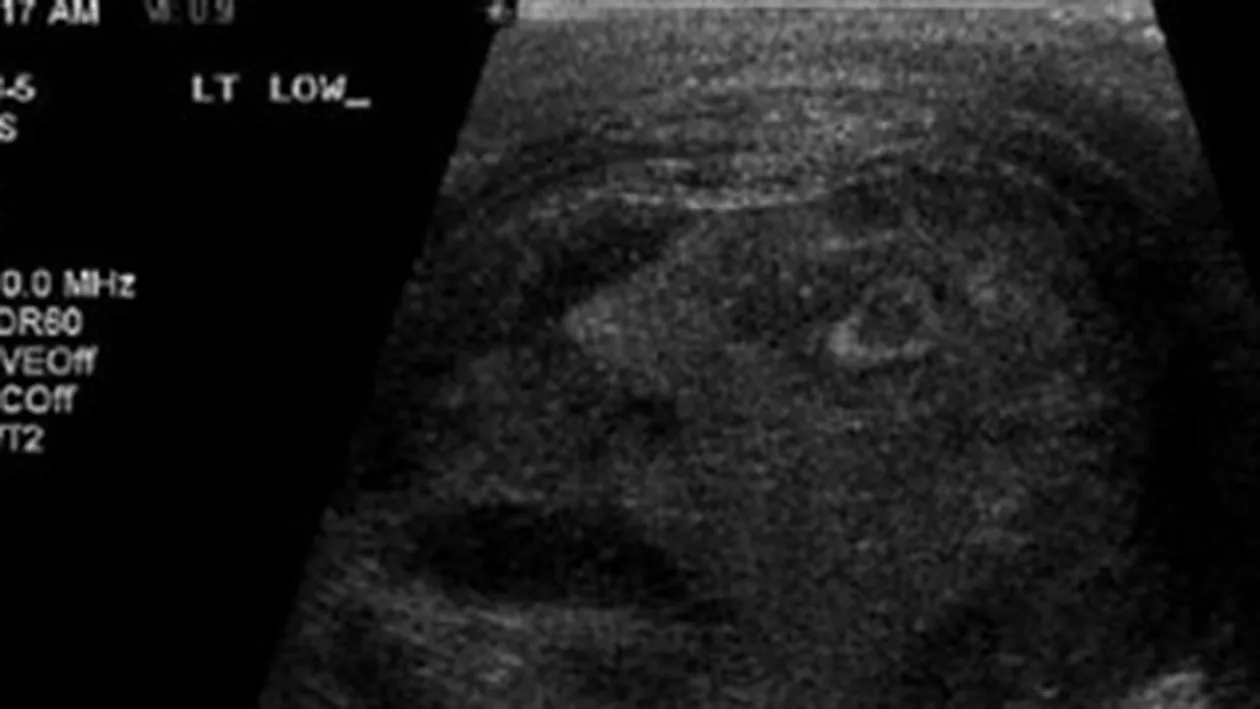

Niste urologi din Canada care-i faceau unui barbat de 45 ani cu o tumoare la testicule un test cu ultrasunete au ramas fara cuvinte cand au vazut in ecografie un chip uman.

In imaginea rezultata in urma analizelor, se poate vedea cu usurinta fata unui om, care pare sa fie chinuit de ceva. „Personalul a fost uimit sa gaseasca conturul unei fete umane, cu privirea indreptata in sus si gura cascata, intr-o expresie care parca arata suferinta severa a acestuia”, au scris medicii in raportul lor. Pentru ca nu au putut accepta sa catalogheze imaginea din ecografie drept o aparitie miraculoasa, doctorii au publicat-o intr-un jurnal de specialitate, in speranta ca unii dintre colegii lor de breasla vor gasi o explicatie stiintifica. Pana acum, insa, nimeni nu a putut elucida misterului chipului din ecografie.